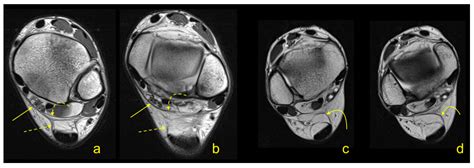

To diagnose issues related to the flexor retinaculum, medical professionals typically perform a physical examination. The Tinel’s sign test—tapping over the area of the retinaculum to elicit tingling in the foot—is a standard diagnostic indicator. Imaging studies such as Ultrasound or MRI are frequently used to visualize the thickness of the retinaculum and identify any cysts, scar tissue, or anatomical variations that may be contributing to nerve compression.